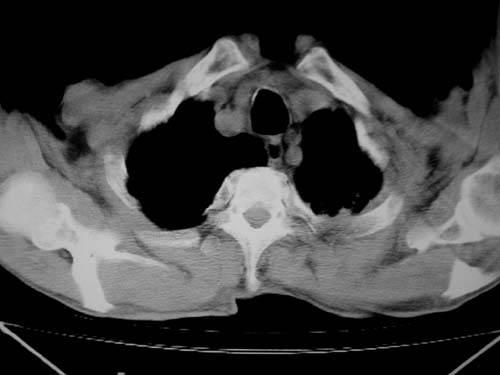

标题: CT19736:男,76岁,咳嗽,胸痛 [打印本页]

标题: CT19736:男,76岁,咳嗽,胸痛

支持左上肺周围型肺癌性并空洞形成伴胸椎转移。

左上沟癌空洞形成并胸椎转移。

左上肺癌性空洞伴胸椎转移。